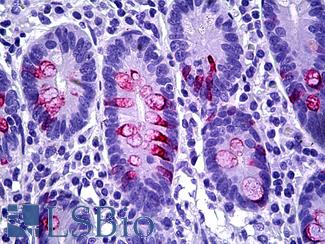

Anti-MUC2 antibody IHC of human intestine. Immunohistochemistry of formalin-fixed, paraffin-embedded tissue after heat-induced antigen retrieval. Antibody LS-B5562 dilution 1:100.

MUC2